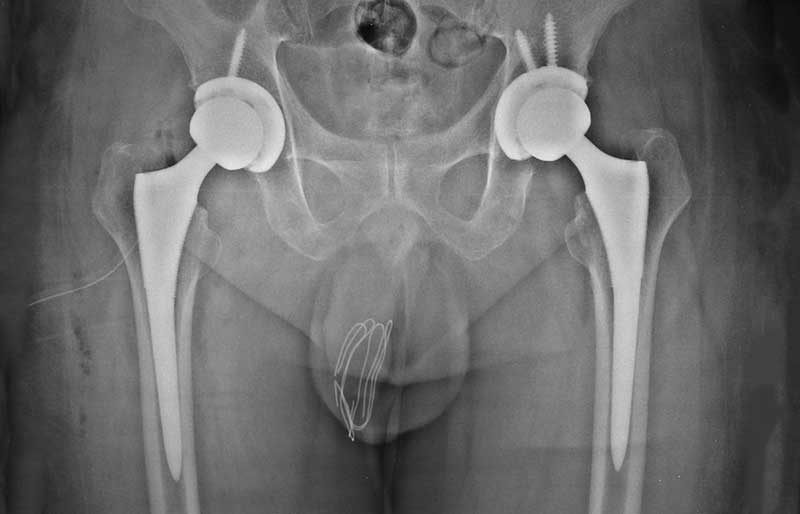

Operasi penggantian sendi panggul adalah suatu operasi untuk mengganti sendi panggul yang rusak dengan sendi buatan yang disebut prosthesis. Penyebab utama kerusakan sendi panggul adalah osteoartritis (baca penjelasan tentang “Osteoartritis”) dan sendi panggul adalah sendi terbanyak kedua setelah lutut yang terserang penyakit ini.

Operasi penggantian sendi panggul merupakan pengobatan terbaik untuk osteoartritis panggul stadium yang berat. Ada empat tujuan operasi ini, yaitu menghilangkan rasa sakit sendi yang telah rusak, memperbaiki lingkup gerak sendi yang sebelumnya kaku dan terbatas, mengembalikan kemampuan penderita melakukan aktivitas harian tanpa rasa sakit, dan meningkatkan kualitas hidup sehingga penderita kerusakan sendi dapat menjalani hidup secara aktif bebas dari nyeri sendi panggul.